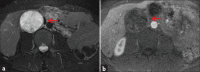

Schwannomas are benign soft-tissue tumors that arise from peripheral nerve sheaths throughout the body and are commonly encountered in patients with neurofibromatosis Type 2. The vast majority of schwannomas are benign, with rare cases of malignant transformation reported. In this pictorial review, we discuss the magnetic resonance imaging (MRI) appearance of schwannomas by demonstrating a collection of tumors from different parts of the body that exhibit similar MRI characteristics. We review strategies to distinguish schwannomas from malignant soft-tissue tumors while exploring the anatomic and histologic origins of these tumors to discuss how this correlates with their imaging findings. Familiarity with the MRI appearance of schwannomas can help aid in the differential diagnosis of soft-tissue masses, especially in unexpected locations.